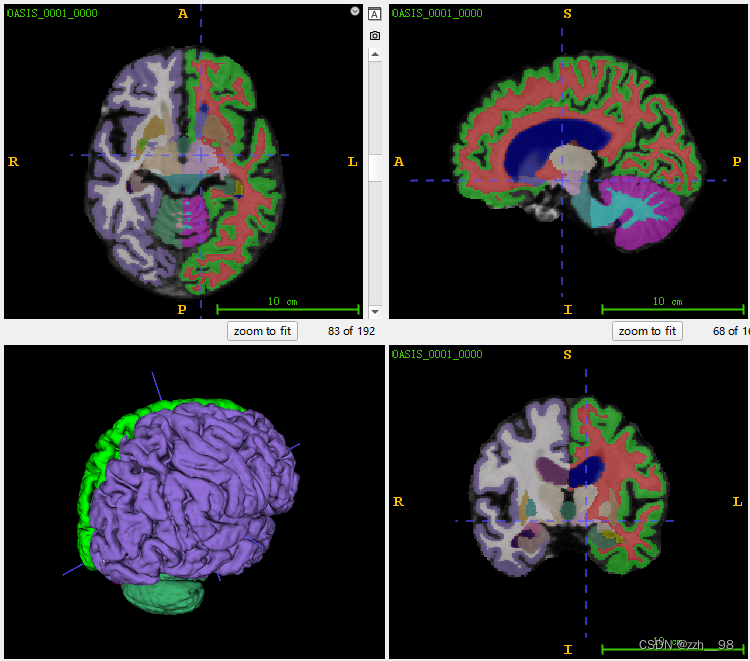

下图为由ITK-SNAP可视化的脑区标签示例:

在该数据集中将脑区分为35个区域,通过与FreeSurfer/SAMSEG处理结果对比得到对应类别如下: